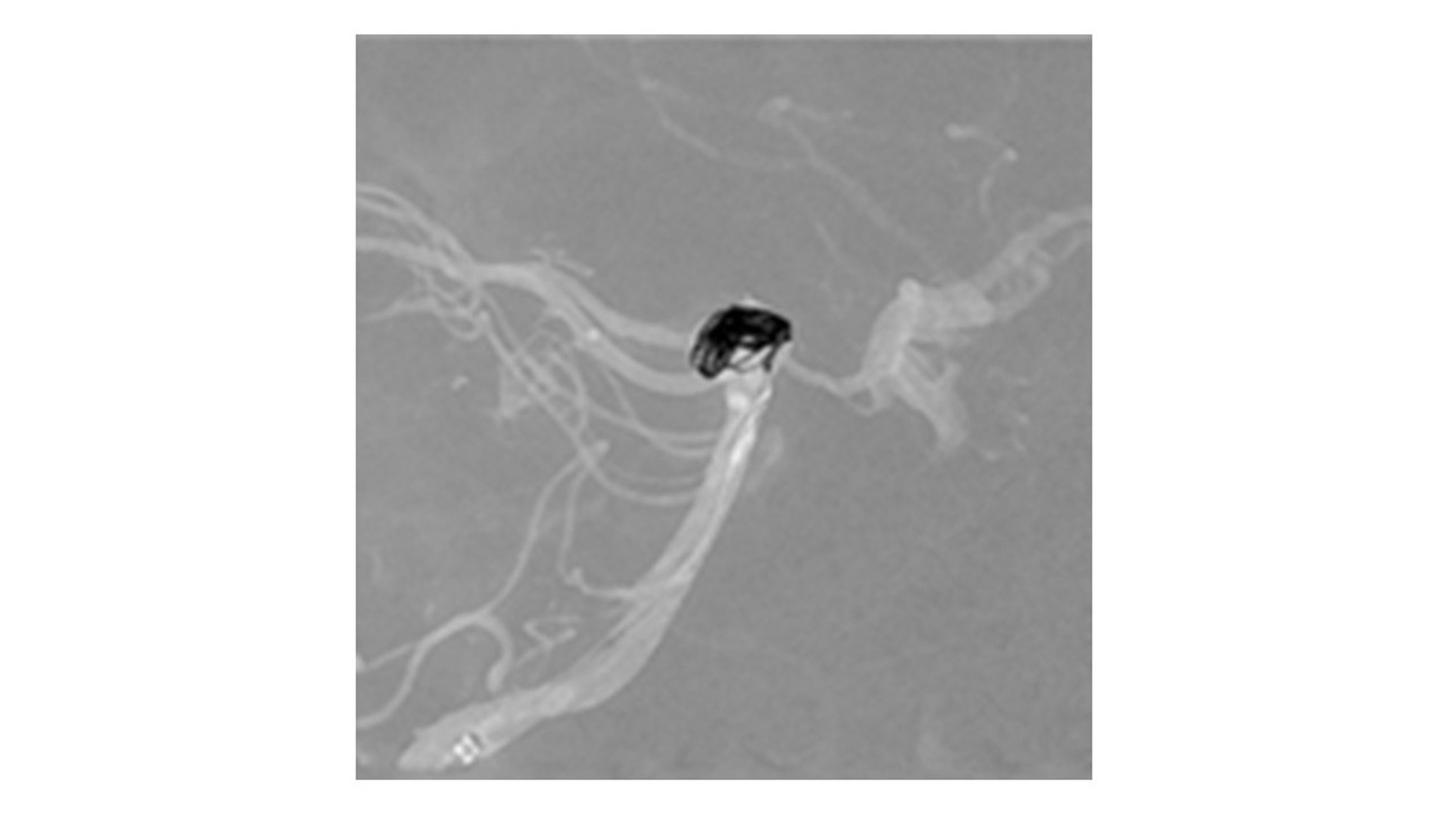

During minimally invasive procedures, it is critical to have a clear view of anatomies and devices. Yet complex imaging tasks or challenging patient conditions often impact image quality. OPTIQ AI delivers constant image quality1 defined by CNR in support of the ALARA principle, independent of patient or C-arm angulation. On top, an AI-powered algorithm reduces image noise in real time across different 2D imaging modes.

Make AI-powered imaging and clear insights your standard during interventions – with OPTIQ AI.